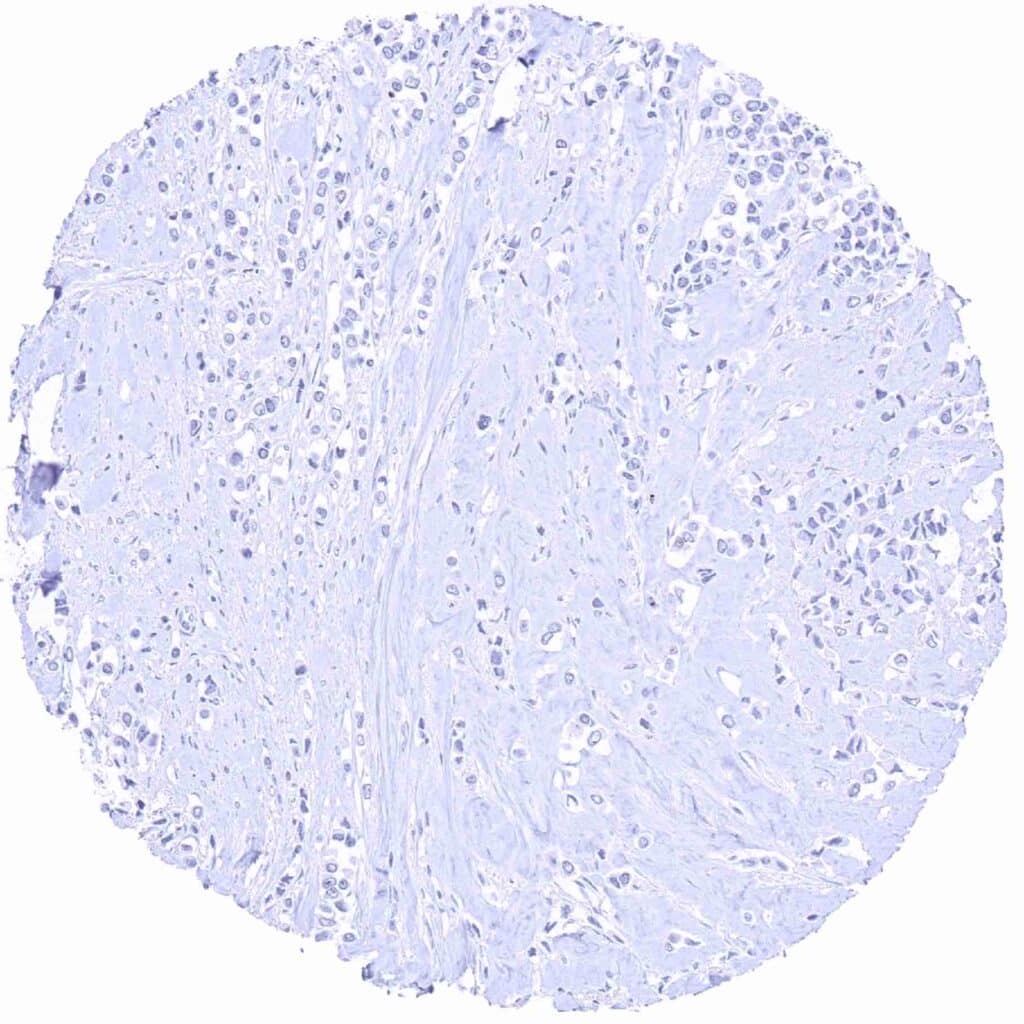

Prostate – Prostein negative small cell carcinoma